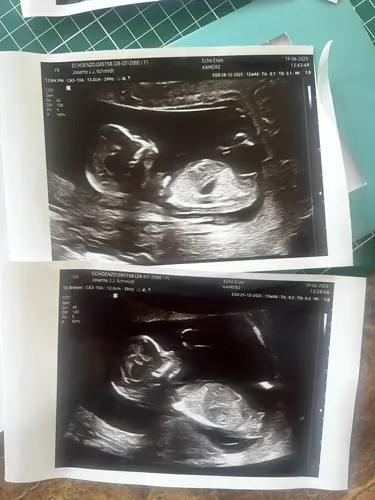

Fijn nieuwe topic! De vorige was veel scrollen ;p heb al van twee dames hier begrepen wat zij denken van mijn nieuwe echo foto maar toch benieuwd wat meerdere dames denken?